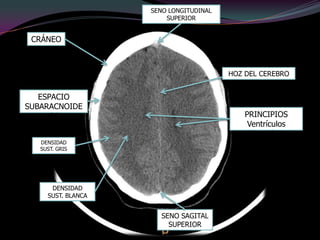

Imagenología(TAC) Cerebro | PPT